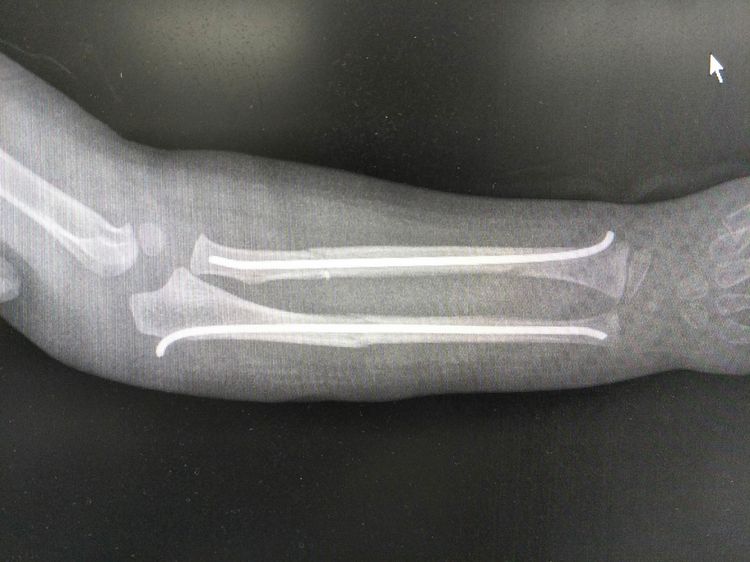

术后拍片复查,尺桡骨骨折端复位良好,内固定克氏针位置良好,均在髓腔内。

术后一个月拍片复查,内固定克氏针位置良好,骨折端对位对线好,骨折端骨痂生长。